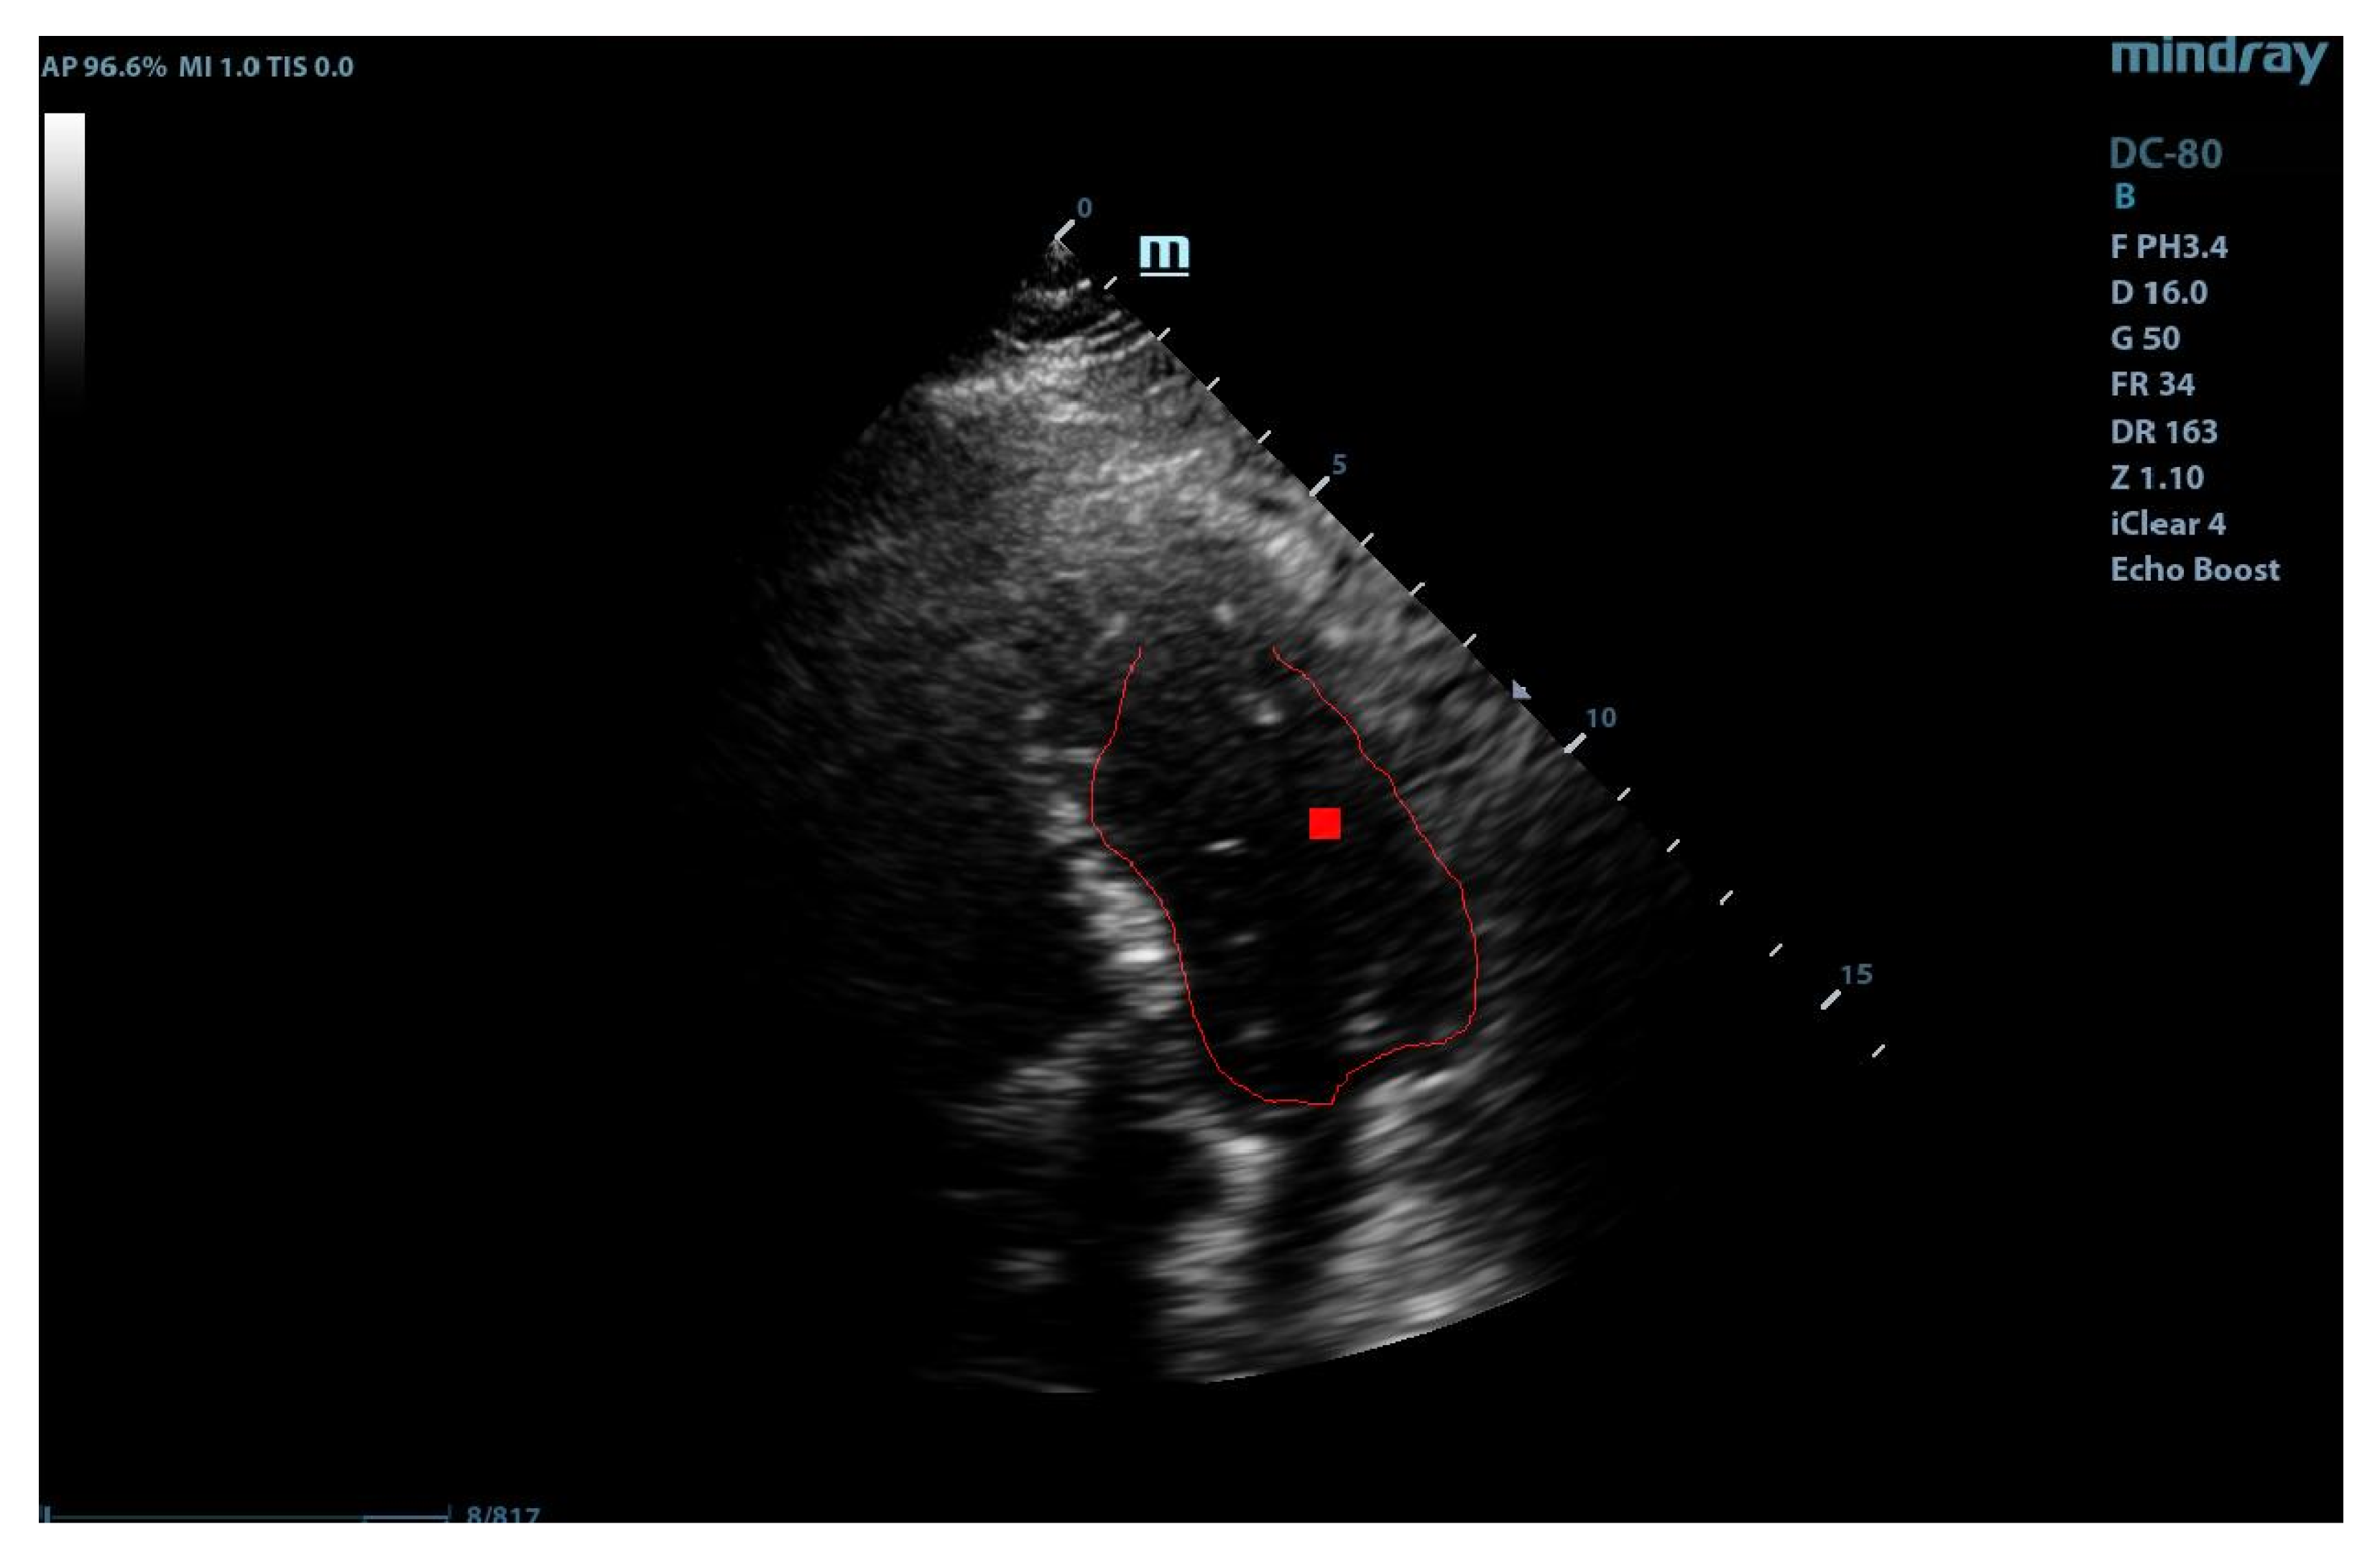

The localization of a region of interest (ROI) on the echographic image is of crucial importance for accurate application of the GHT. The correct marking of ROI eliminates most of the detection problems encountered by the GHT. For the detection of the application area, we employed a Gabor-like filtering. The Gabor-like filtering gave us a corresponding region of interest for the application of the GHT (see Figure 3).

By combining the two paths, we obtained the final marking of the left ventricle (see Figure 5). The marking of the left ventricle wall can be observed following the thin red line.

Figure 3. ROI after Gabor-like filter.

Figure 5. Complete application of the anisotropic Gabor–Hough transform.